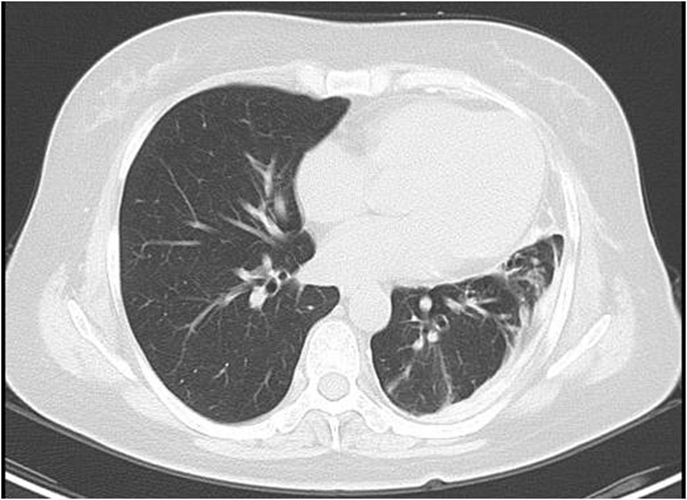

肺腺癌圖片

中分化肺腺癌

右上肺腺癌

右下肺腺癌 的